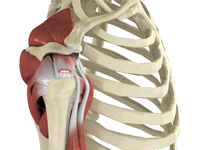

Normal Anatomy of the Shoulder Joint

The shoulder is the most flexible joint in the body making it the most susceptible to instability and injury. It is a ‘ball-and-socket’ joint. A ‘ball’ at the top of the upper arm bone, humerus, fits neatly into a ‘socket’, called the glenoid, which is part of the shoulder blade, scapula.

The shoulder joint is made up several bones and soft tissues. It has three bones, the collarbone (clavicle), scapula, and humerus.

Humerus provides attachment to muscles of the upper arm. Scapula is the bone that connects the upper arm bone with the collarbone. It is a flat bone and roughly triangular in shape and provides attachment to the muscles of back and neck.

The clavicle is an S-shaped short bone that connects the shoulder girdle to the body (trunk). It supports the shoulder in a functional position with the axial skeleton so that the arm has maximum range of movement. It also protects major underlying nerves and blood vessels as they pass from the neck to the axilla.

The coracoid process is the extension of the scapula around the shoulder joint at the front portion of the scapula. The acromial process is the extension of scapula around the shoulder joint at the back that forms a roof, acromion.

Glenoid is the smooth shallow depression at the end of scapula that forms the socket of shoulder joint.